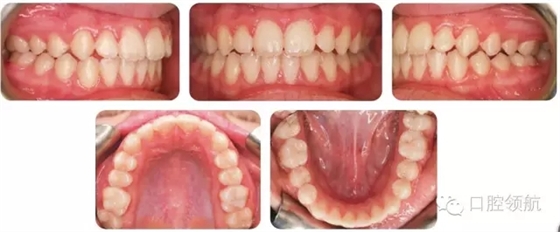

考慮拔牙牙位時(shí),一般會(huì)選擇多生牙;但也要仔細(xì)評(píng)估正常牙和多生牙的冠根解剖,再?zèng)Q定拔牙牙位。這個(gè)病例中,更靠遠(yuǎn)中的側(cè)切牙(多生牙)被拔除。圖2.2是經(jīng)過功能矯治和固定矯治后的最終口內(nèi)像。

圖2.2